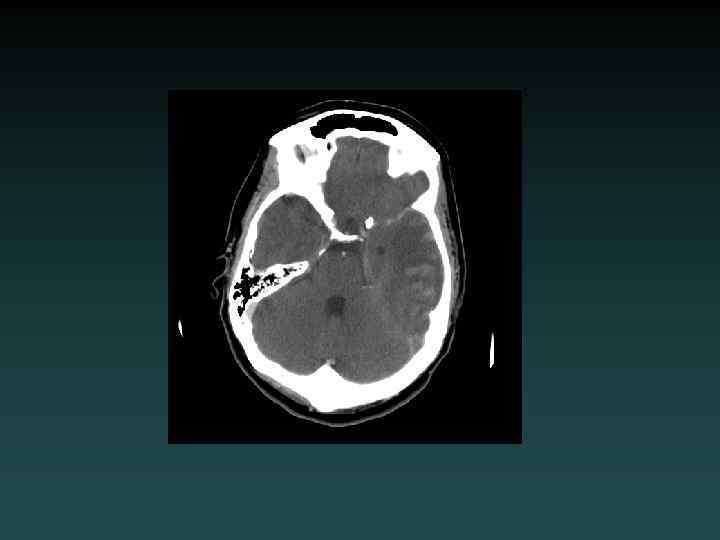

Subarachnoid Hemorrhage • Subarachnoid – Sulci – Cisterns – Ventricles • Trauma – lateral convexities • Aneurysm – basal cisterns • Interpeduncular Cistern – most sensitive

Aneurysmal SAH • Sudden severe headache • HYPERDENSE CSF spaces • Location – Interhemispheric: ACo. A – Sylvian: MCA • HYDROCEPHALUS, VASOSPASM and ISCHEMIA – MUST find the aneurysm! • DSA, CTA and/or MRA